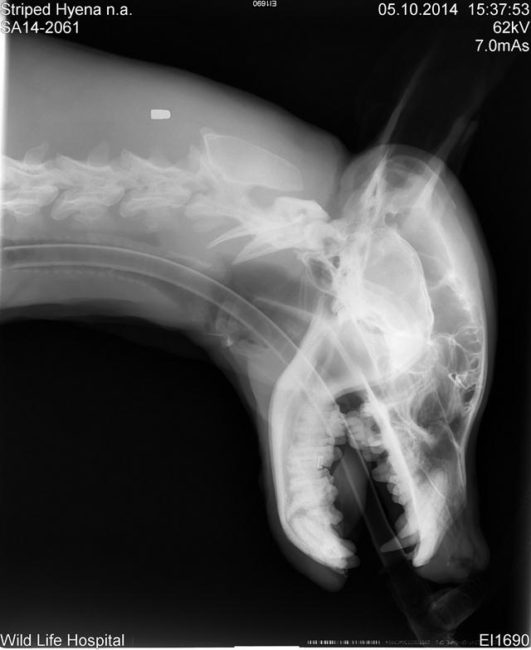

Οι κτηνίατροι προσπάθησαν να σταθεροποιήσουν την κατάσταση της ύαινας καθώς έκαναν διάφορες εξετάσεις για να καταλάβουν το πλήρες εύρος των τραυμάτων της. Ενώ μπορούσαν εύκολα να αναγνωρίσουν τους εξωτερικούς τραυματισμούς, δεν είχαν ιδέα τι συνέβαινε μέσα στο καημένο πλάσμα.

Σύντομα όμως κατάλαβαν πως κάτι δεν πήγαινε καλά. Είδαν πολλές μελανιές στο σώμα της και υποπτεύθηκαν πως είχαν δημιουργηθεί από ξυλοδαρμό.

Οι μελανιές όμως δεν ήταν τα μόνα της τραύματα. Είχε πολλά σπασμένα δόντια επίσης. Κάποια ήταν κομμένα μέχρι τη ρίζα και αυτό πρέπει να της προκαλούσε φρικτό πόνο.

Τελικά, βγήκαν και οι υπόλοιπες εξετάσεις και έδειξαν πως είχε πολλά σπασμένα κόκαλα σε όλο του το σώμα.